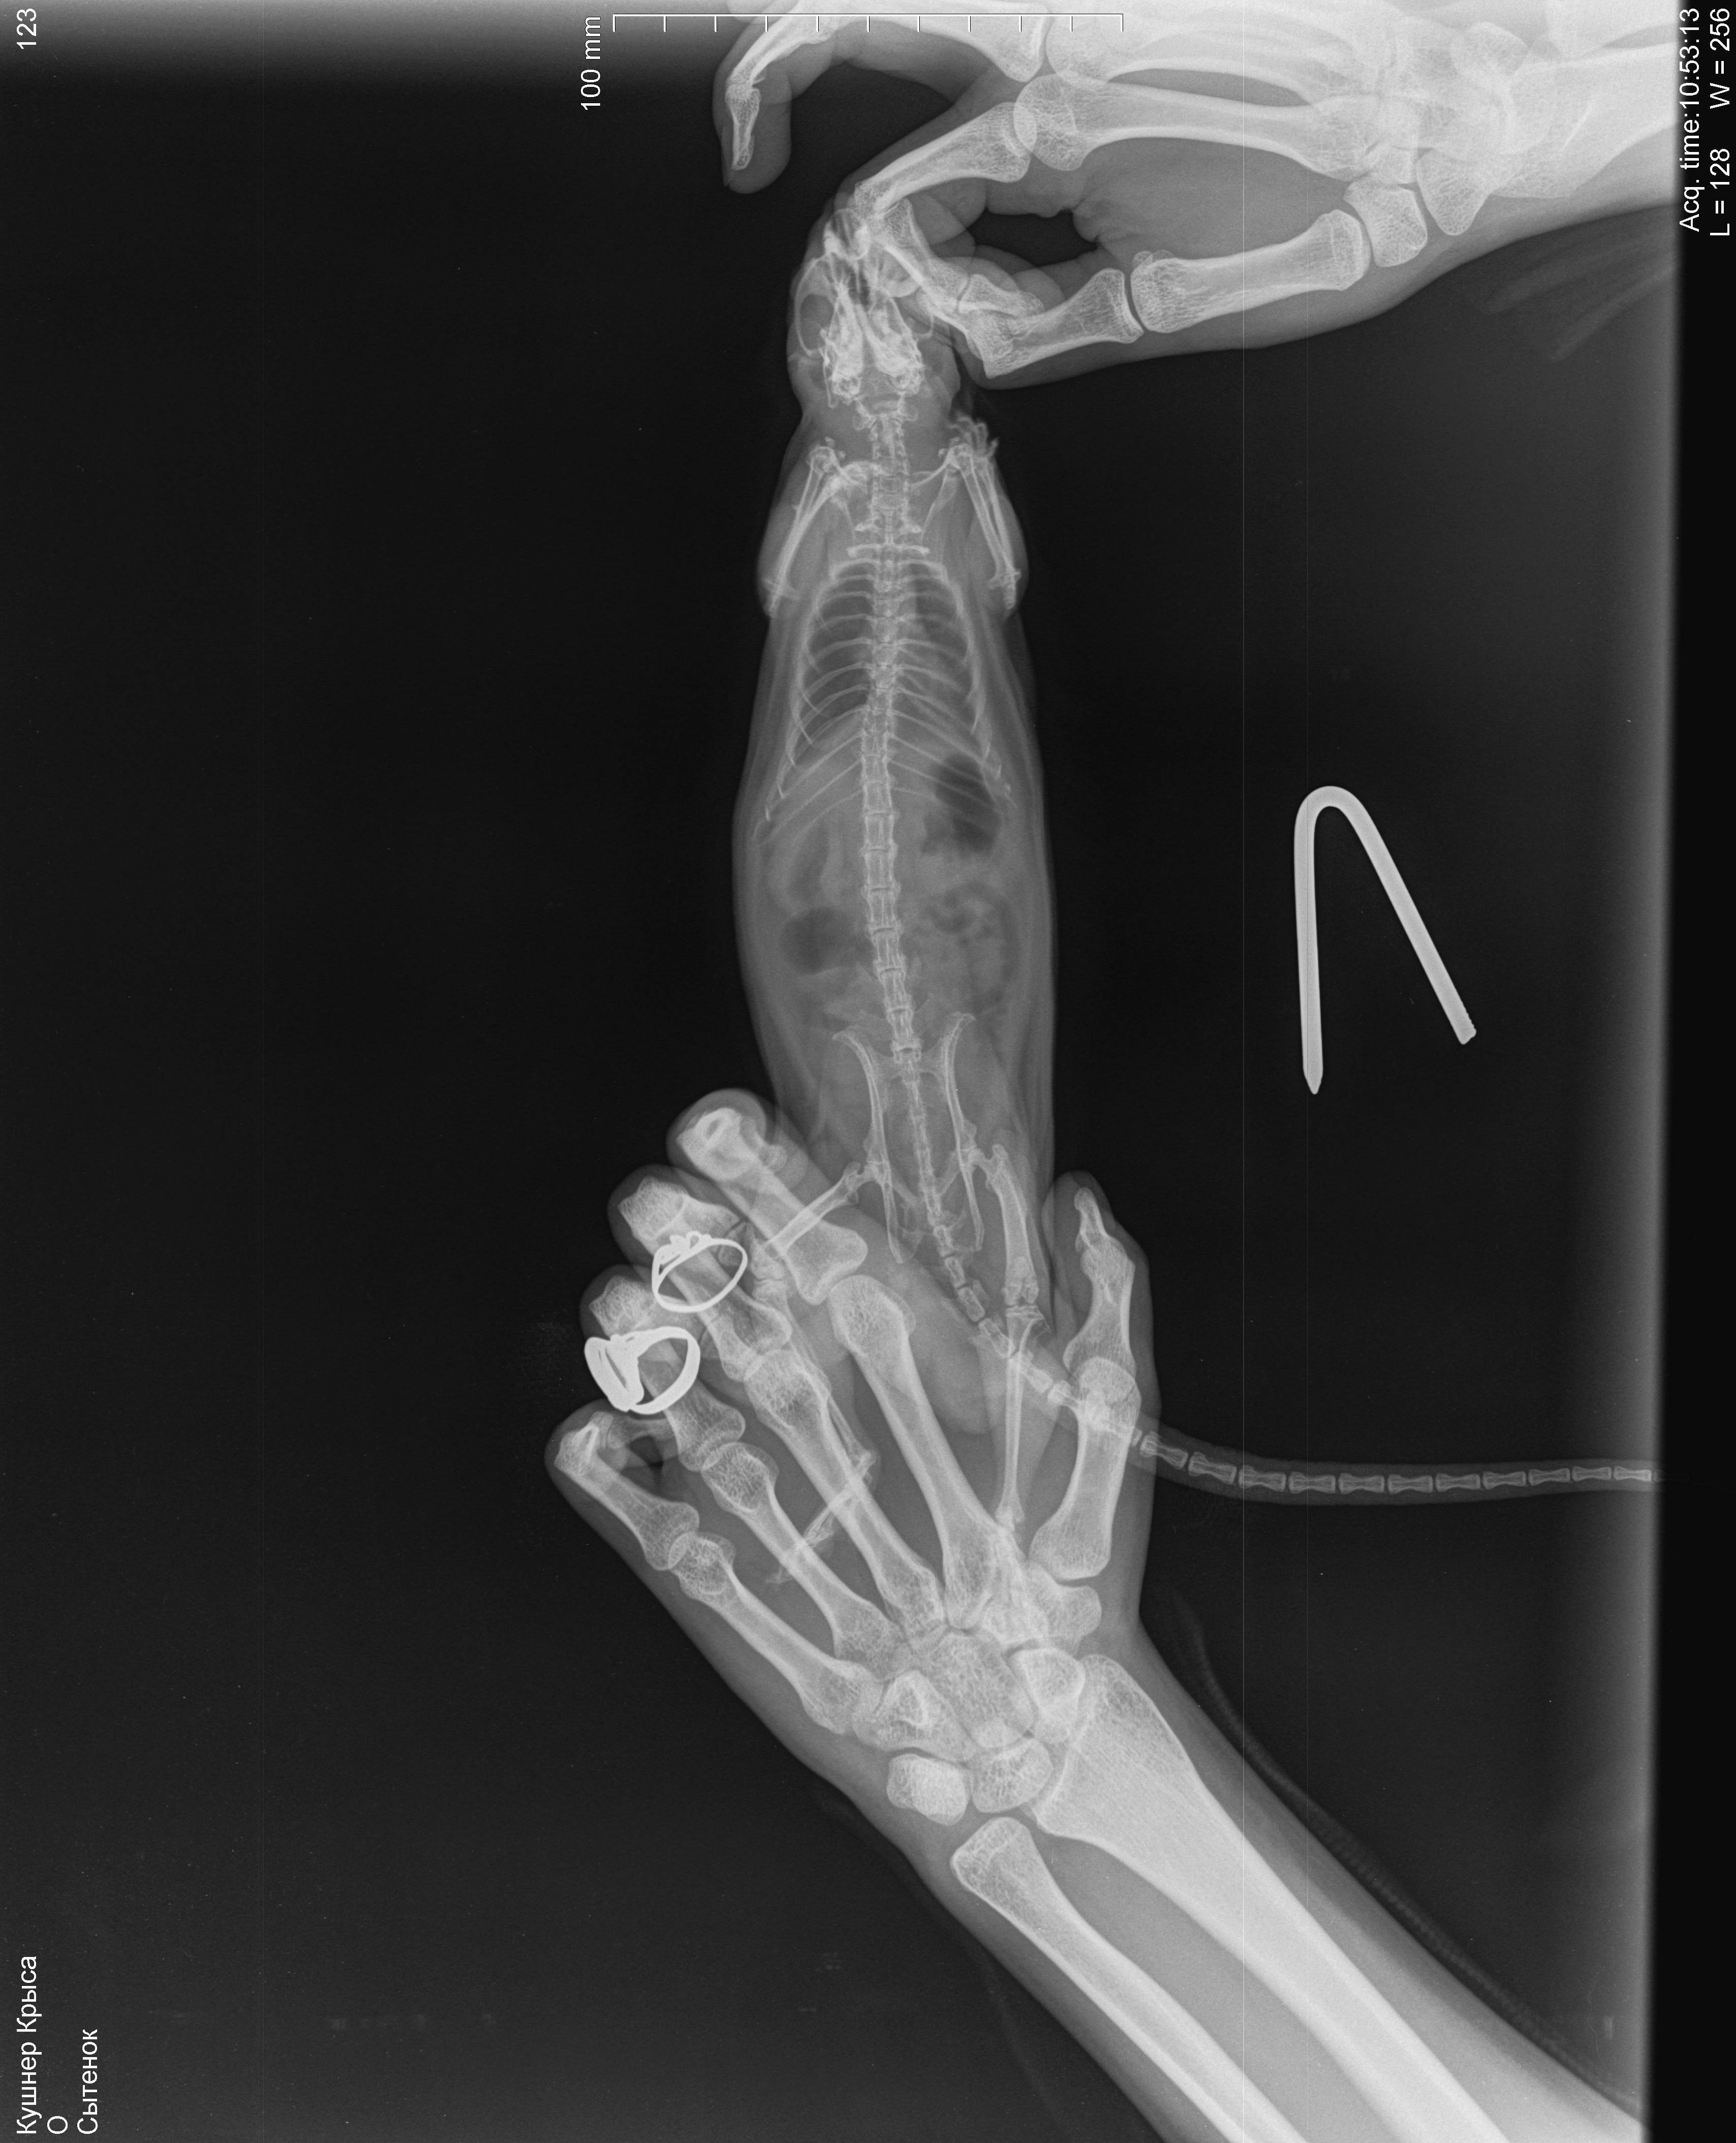

6 декабря свозила к ветеринару, послушали - услышали хрипы, больше слева, сделали рентген, врач сказала, что вероятнее всего пневмония, назначила синулокс 0,15мл в/м 1 раз в день, катозал 0,3мл 1 раз в день. По-моему стало немного получше, начал умываться. Дома пару раз пытался попить, но такое ощущение, словно захлебываться начинает и перестает, стал незначительно активнее. 8,9 декабря возила его на оксигенотерапию по 1 разу по 20минут, в состоянии особо изменения не заметила. 10 числа ближе к вечеру - крыса сидит на одном место, тяжело дышит, дышит боками, хрипы более выраженные, голова опущена вниз, беспокойный, в руки не дается. Повезла к другому врачу (рабочее время моего закончилось) - сказал, что вероятнее всего отёк легких, сделал инъекцию дексаметазона 0,05мл в/м. Спросила про диуретики, сказала, что не надо, так как дексаметазон будет выполнять эту функцию в том числе.

Отметил, что если не поможет, то наварное ничего уже не поможет. Сегодня, 11 числа, стало незначительно лучше, поехала к своему врачу, она была на выезде, приняла другая девушка, сказала что не отёк, т.к. хрипы должны быть другие. Назначила ингаляции беродуала и соответственно продолжать назначенную терапию. Я не знаю, продолжать ли терапию, или её стоит поменять или я только мучаю крысу и ей врят ли уже помогут. Есть ли смысл покупать беродуал? Посмотрите на снимки, пожалуйста, действительно ли пневмония, а не онко? В прямой проекции видно затемнение в проекции шейных позвонков, но на боковой его не вижу, врачи сказали, что это надгортанник

, хочется быть уверенной, что не какое-нибудь инородное тело.